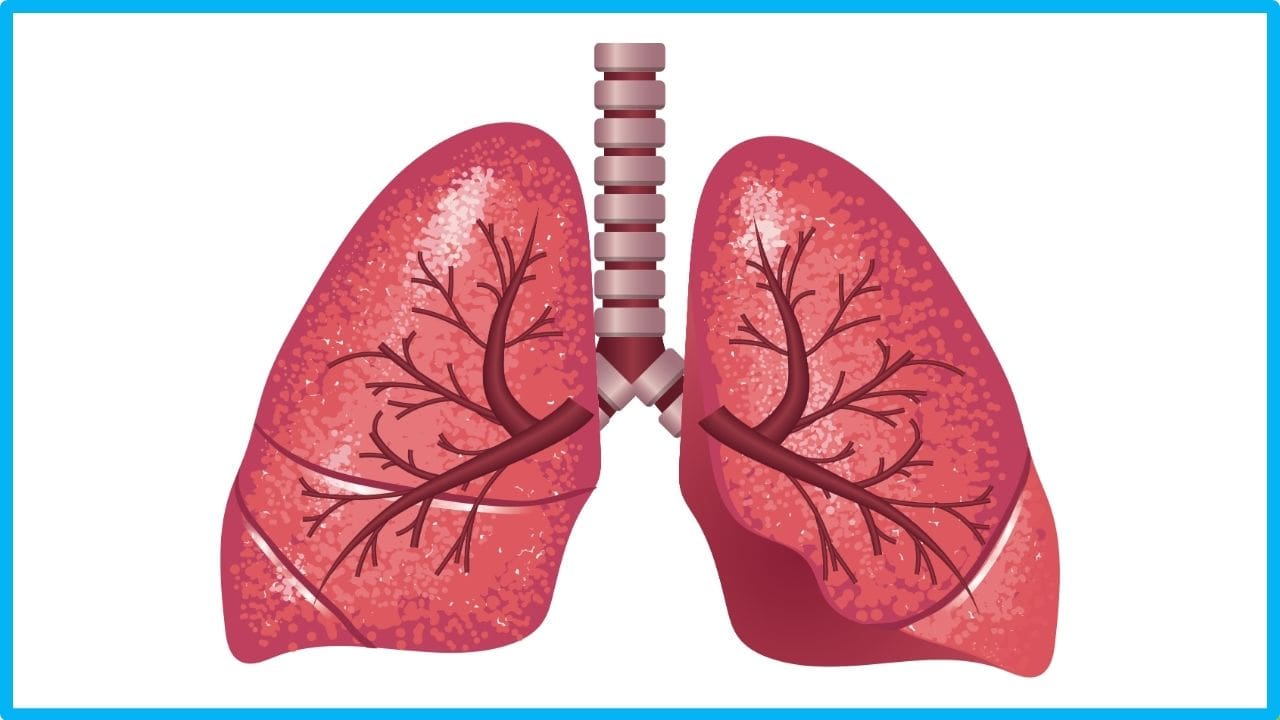

Здоровые Легкие Картинки

Здоровые Легкие Картинки 117 фото